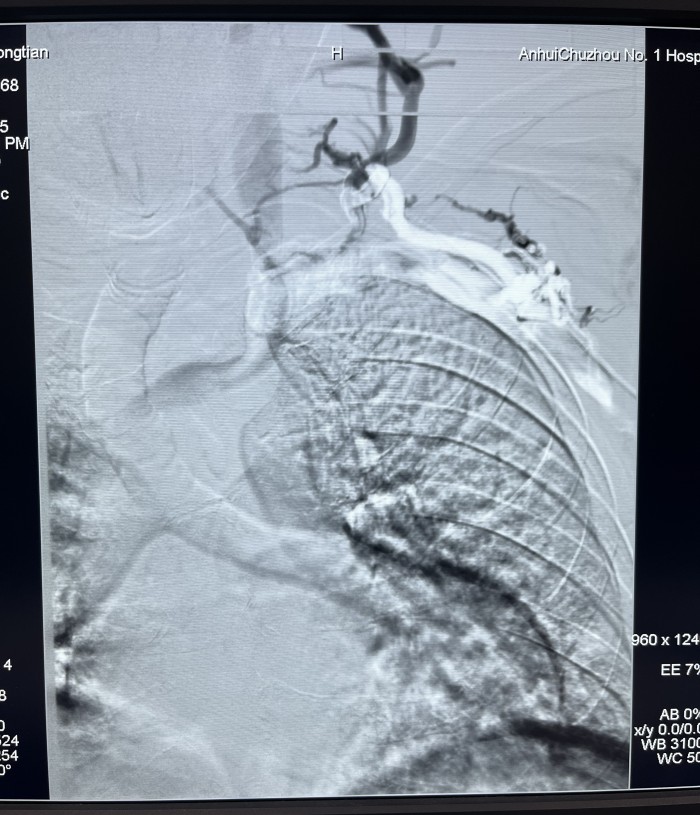

患者赵某,因两侧多囊肾致肾功能衰竭在我院行血液透析三年半。近一年来患者出现血透后左上肢肿胀并伴头面颈部表浅静脉怒张,近三月透析时人工内漏内血流量下降。经我院介入血管科副主任芮兵门诊详细询问病史及查体后收治该患者入院,行左上肢CTV及左上肢静脉造影检查显示:左头臂静脉起始部重度狭窄。在芮兵副主任医疗团队精心制定手术方案,排除手术禁忌后,成功实施了经皮左头臂静脉球囊扩张成形术,术后患者左上肢肿胀明显消退,透析时血流量>200ml/min,可以完成透析。